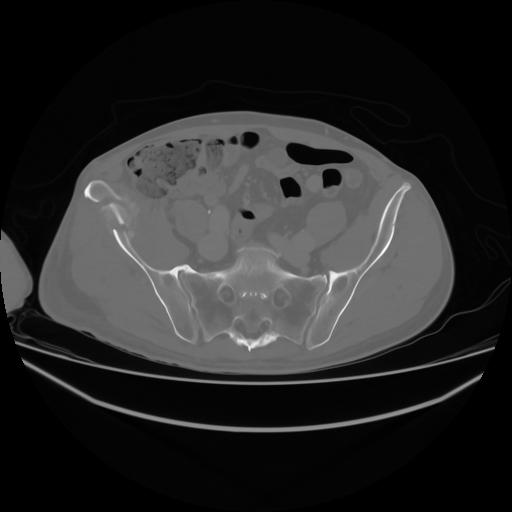

4 CUERPO,CE,Axial,3.0,CUERPO,,